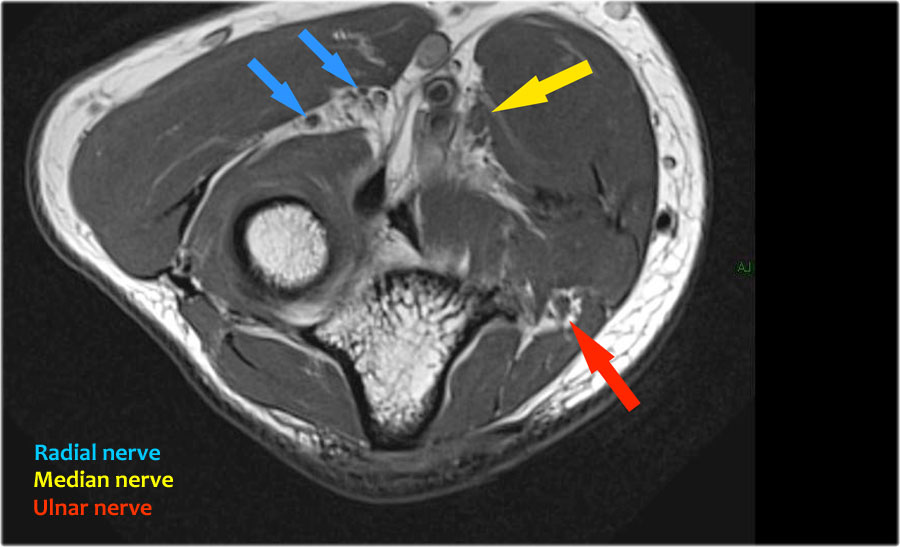

Dây thần kinh quay có thể được xác định rõ nhất ở mức chỏm xương quay, nơi có thể quan sát thấy các nhánh nông và nhánh sâu trong ống xương quay (mũi tên).

This is a very consistent place to find the radial nerve.